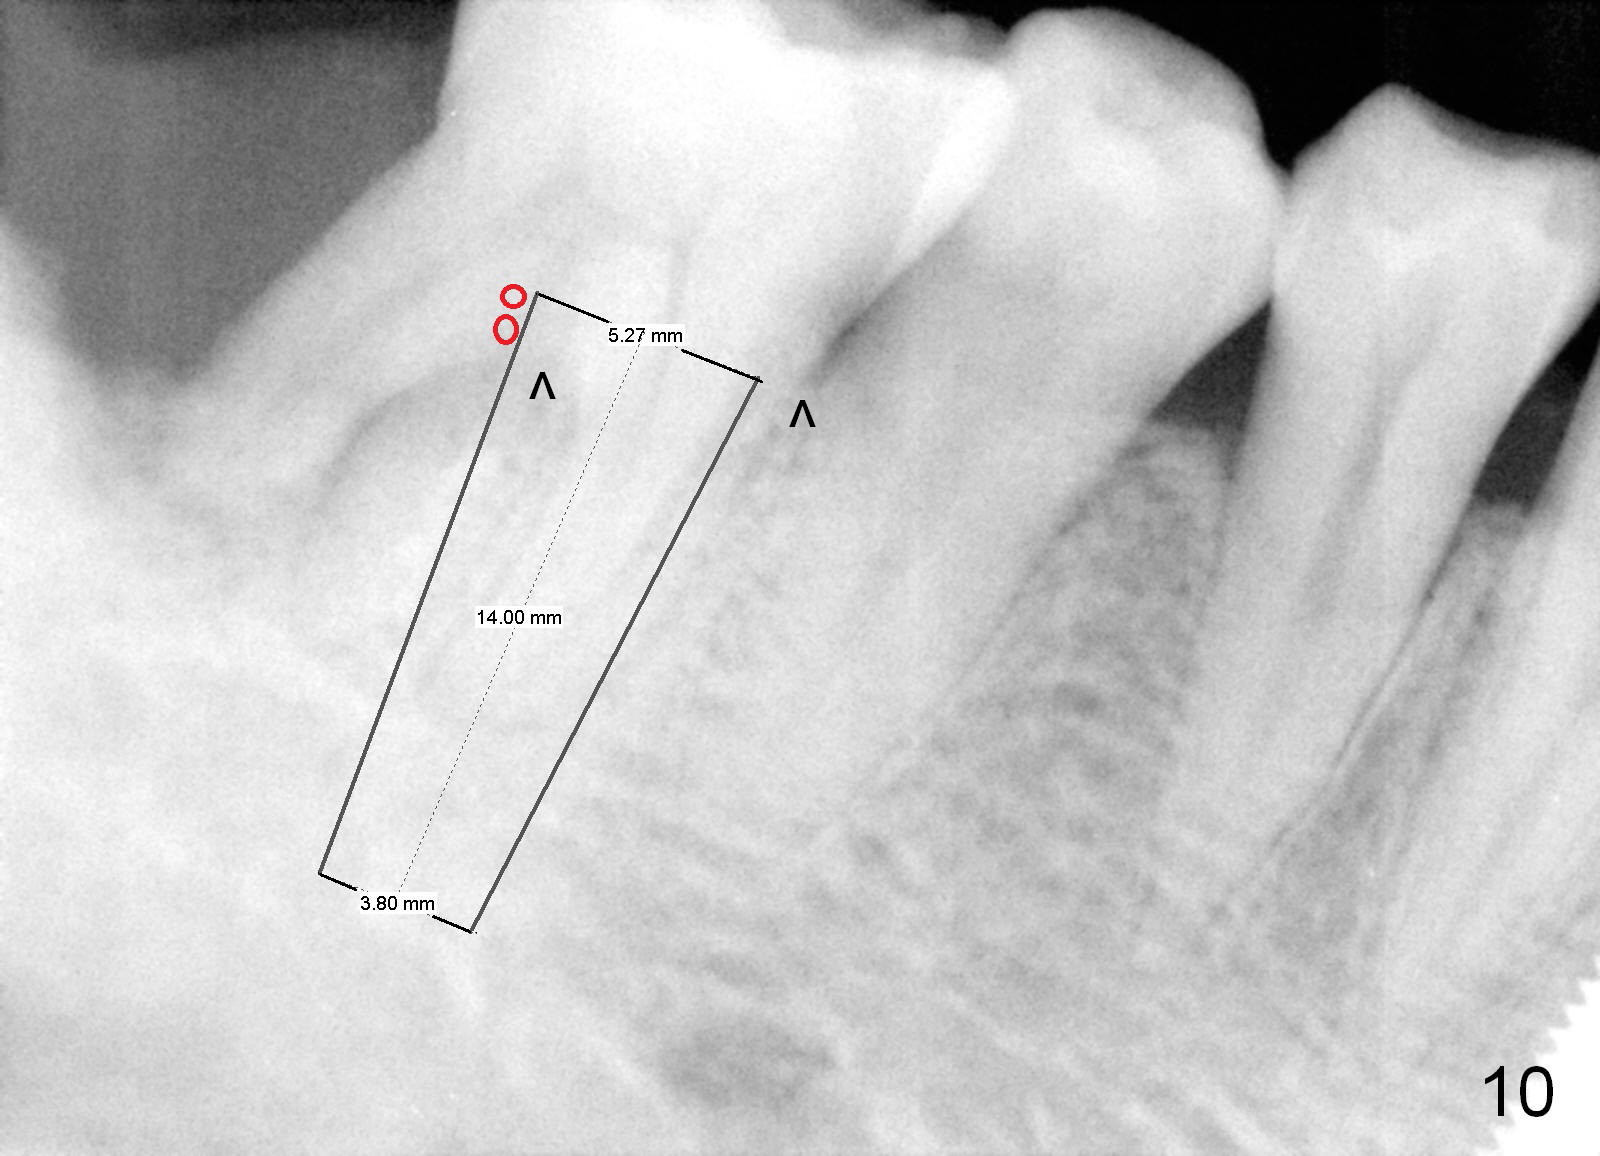

One year and a half years ago, the tooth #31 of a 48-year-old man had infection (Fig.1 *) and was extracted without implant.  There was more bone loss in the distal of #30 than in the mesial (Fig.2 *).  Recently the patient returns with infection at #30 distally with severe bone loss (Fig.3 *).  An immediate implant is to be placed mainly in the mesial socket (Fig.4 (bone-level), Fig.5 (tissue-level)).

Fig.6 is an illustration after extraction (S: septum; M: mesial socket).  Osteotomy is initiated with a pilot drill in the distal aspect of the mesial socket or the mesial aspect of the septum (Fig.7).  The osteotomy is enlarged with osteotomes; at the same time the septum is being pushed distally (Fig.8 blue arrow) with leaning the osteotomes distally (white arrow).  When an implant is placed, the apex is mainly seated in the mesial socket, while the coronal end is more or less inclined distally for restoration.  The apical half of the distal sockets is packed with collagen plug or dressing, whereas the remaining sockets and coronal exposed threads are filled with bone graft (Fig.9,10 red circles).  An incision is made if needed for better visibility.   The most coronal socket is going to be obliterated by a cemented or healing abutment.  Does the treatment planning help surgery?